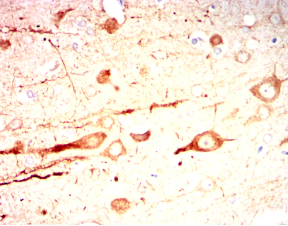

IHC    1/200 - 1/1000